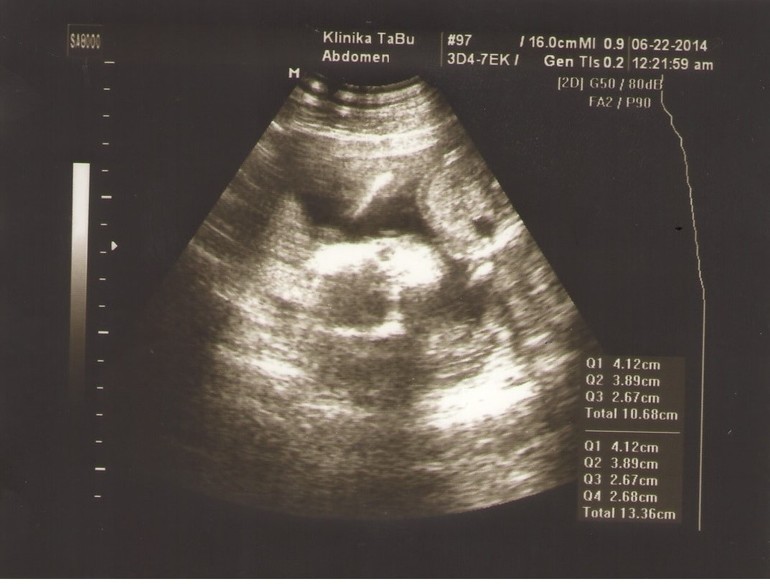

то что ближе к левой части, большое белое — это головка, смотрит на вас, если присмотреться, то есть 2 черных шарика, один выше, другой под ним, это глазки, левее получается виден серый лоб, а правее все белое —  это челюсти и подбородок. белая полоса сверху поду углом — это ручка. а большой шар справа и выше — это животик, черный шарик снизу в нем — это желудок. и рядом с желудком еще белая полоса горизонтально в верх — это ребра, а ниже белая палочка небольшая — это вторая ручка 10e47aab1f60d8020b6878d907de60fc.jpg

фотография действительно не самая удачная, но продолжайте вглядываться! и вы найдете на лице глазки, особенно правый, его лучше видно, рядом с рукой ( сверху), рука к виску направлена, а вот левый (нижний) сложнее, он не ровно под верхним (правым), а чуть правее, так как головка под наклоном:))) а над глазиком даже надбровная дуга видна (у нижнего глаза левее темного пятна видна белая полоса) пытайтесь, вглядывайтесь:) и дорисовывайте в мыслях:)

Мне кажется,что лежит спинкой кверху. Справа голова,вниз-носик и сосет кулачек)))А на правую ручку опирается. Ножек почти не видно-очень расплывчато...

Мне тоже кажется, что слева ножки, внизу одна ручка, вверху вторая, посередине туловище, а голова повернута лицом к нам и вон глазки видно. А вообще, фотки конечно жесть))) Аппарат у них что ли старый там?

По центру туловище, лежит так сказать на спинке, вид сбоку, а ещё ручки — одной машет мамке, на другую облакачивается. От шо я вижу  super_smilies086.gif не бейте если что  super_smilies082.gif

то что справа голова не уверена,как то странно она лежит получается)

а не может это быть просто не удачно сфоткано личико? ме напрмер по центру кажется что вижу глазки,носик и ротик) просто нам лицо фоткали тоже и я примерно могу разобрать,если это оно))) вот если голову на правое плечо положить себе и в цент посмотреть)

Говор вот мужу тоже, видится мне лицо прям по центру! А он — а справа что круглое??? Вот я и не знаю уже! big_smiles_162.gifУ других посмотришь все ясно и понятно!))))